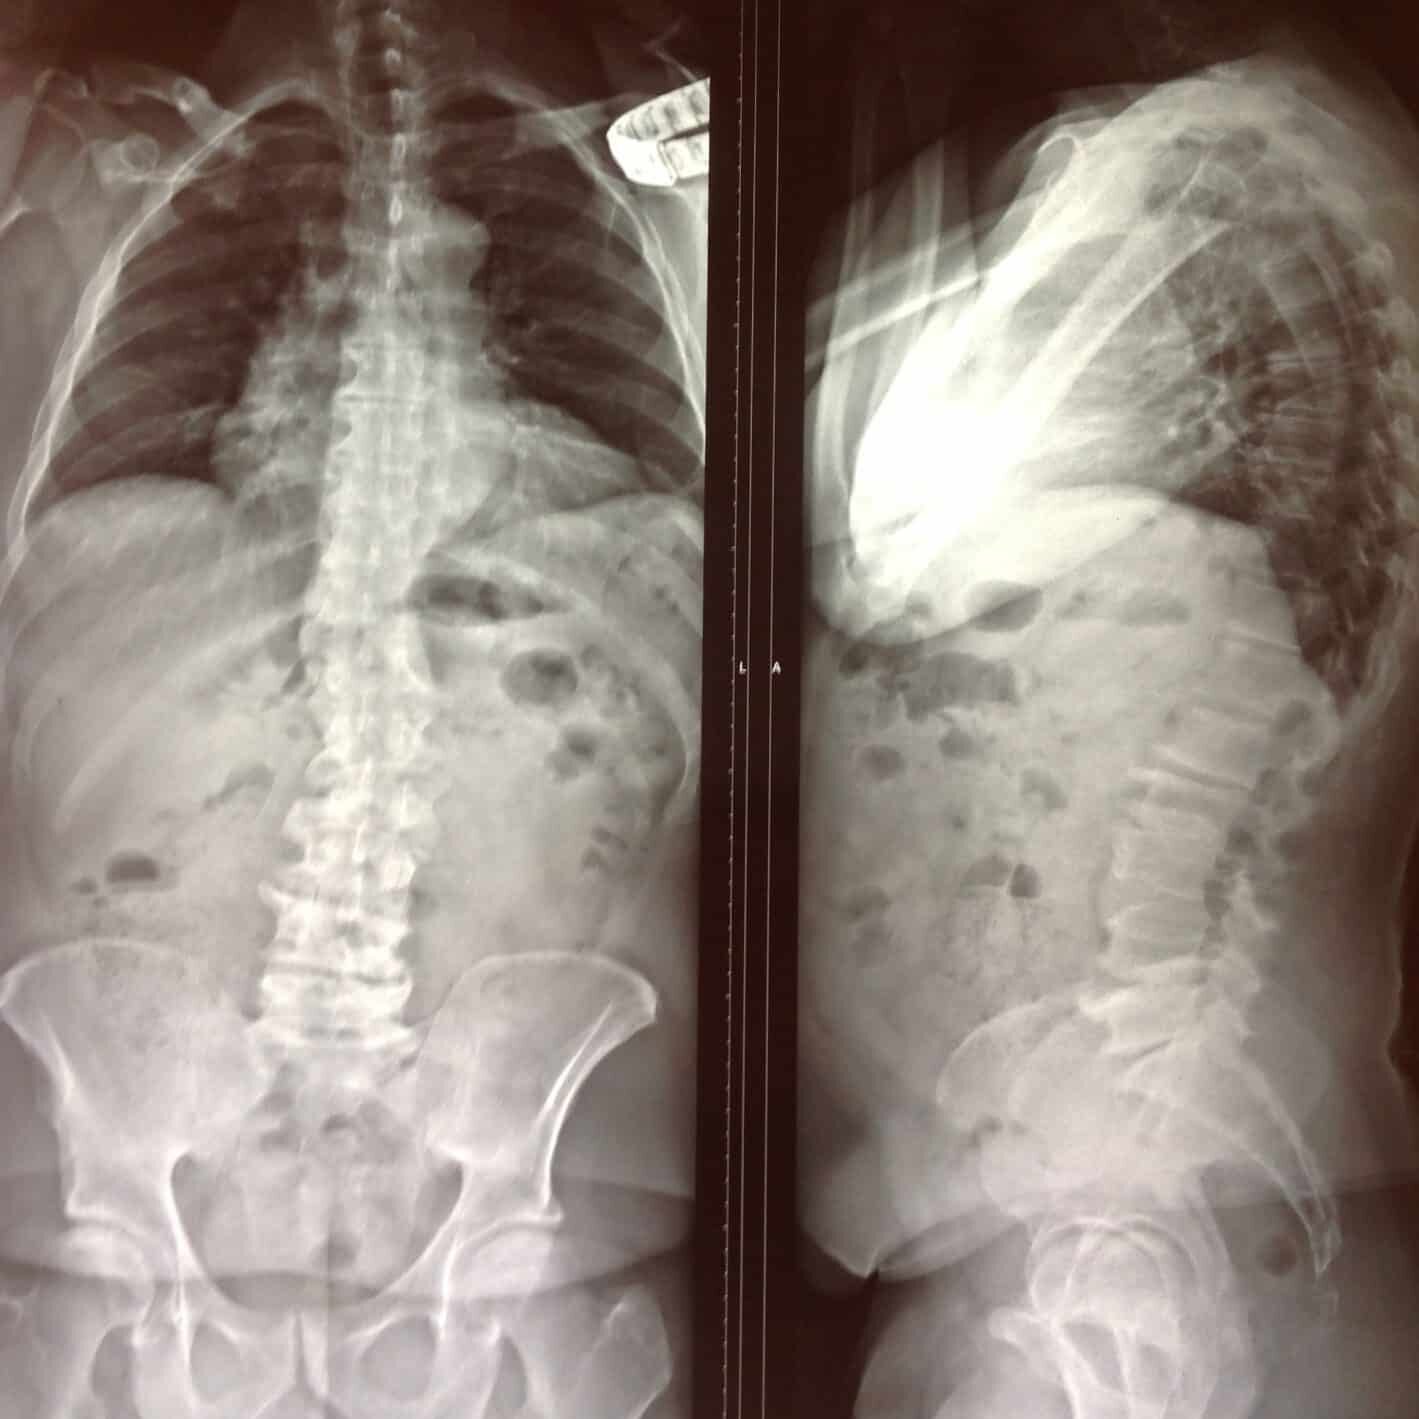

Le patient se présentera à cette première séance muni des imageries de sa colonne vertébrale.